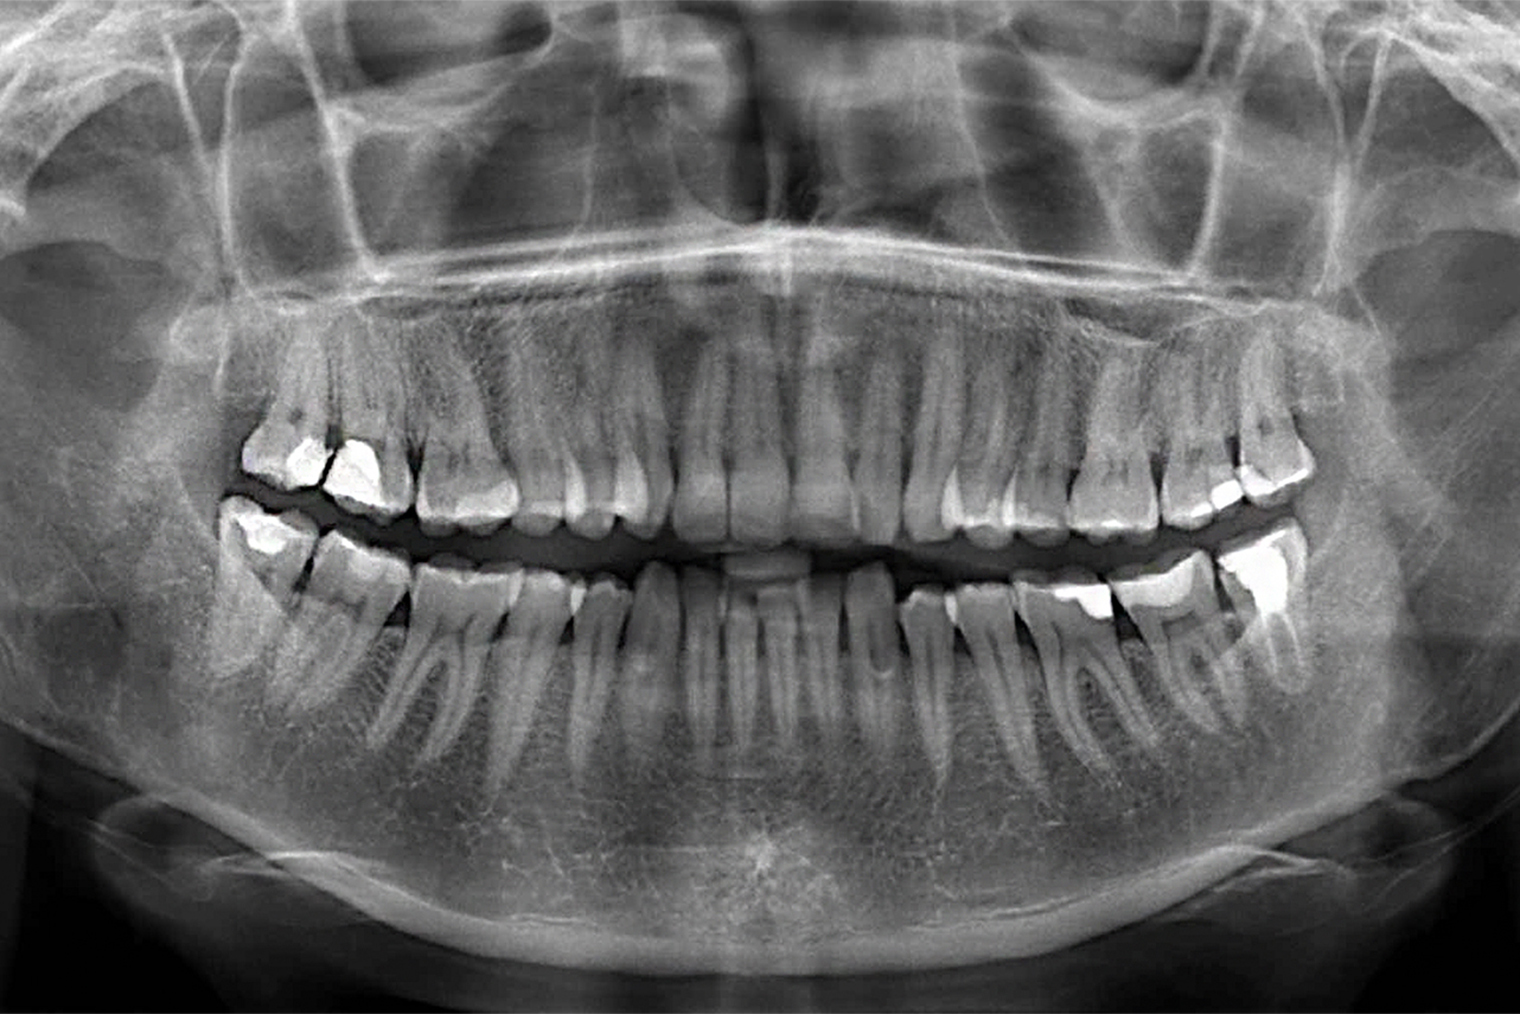

- Сделать панорамный снимок челюсти.

Сделать панорамный снимок челюсти стоит заранее, до первого визита к ортодонту. Он понадобится вам в любом случае. Еще этот снимок называют ортопантомограммой или ОПТГ.